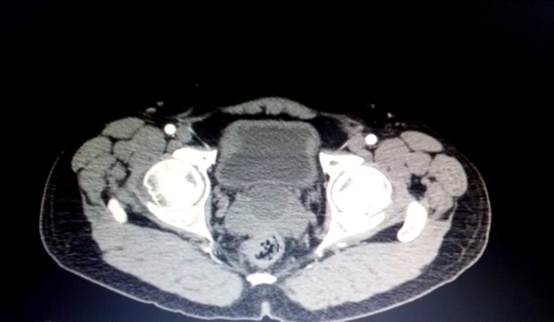

A la exploración física dirigida, los genitales se observaron acordes para su edad, pene no circuncidado, prepucio retráctil, meato uretral central, ambos testes en las bolsas escrotales, sin alteraciones evidentes, próstata hipertérmica, dolorosa, bilobulada, adenomatosa grado II, no se palparon lesiones sospechosas. El tratamiento se inició para prostatitis. El ultrasonido vesicoprostático reportó que la próstata medía 40 x 47 x 35 mm (Figura 1). Se trató de una lesión hipoecoica de 30 x 23 mm en línea media. La lesión se corroboró en el ultrasonido prostático transrectal (Figura 2). La tomografía abdominal contrastada (Figura 3) no reportó anormalidades en la vía urinaria. En la espermatobioscopia destacó la hematospermia. La cuenta espermática se informó con valores normales en concentración, estructura y motilidad.

Figura 3 Imagen de tomografía axial computada abdominal, con contraste venoso. En este corte en fase arterial cerca de la próstata se aprecia una lesion homogénea hipodensa, en la línea media de la grándula prostática. En el resto del parénquima prostático no se encuentran otras lesiones. Se aprecian paredes vesicales, con discreto engrosamiento difuso, sin otras lesiones evidentes.